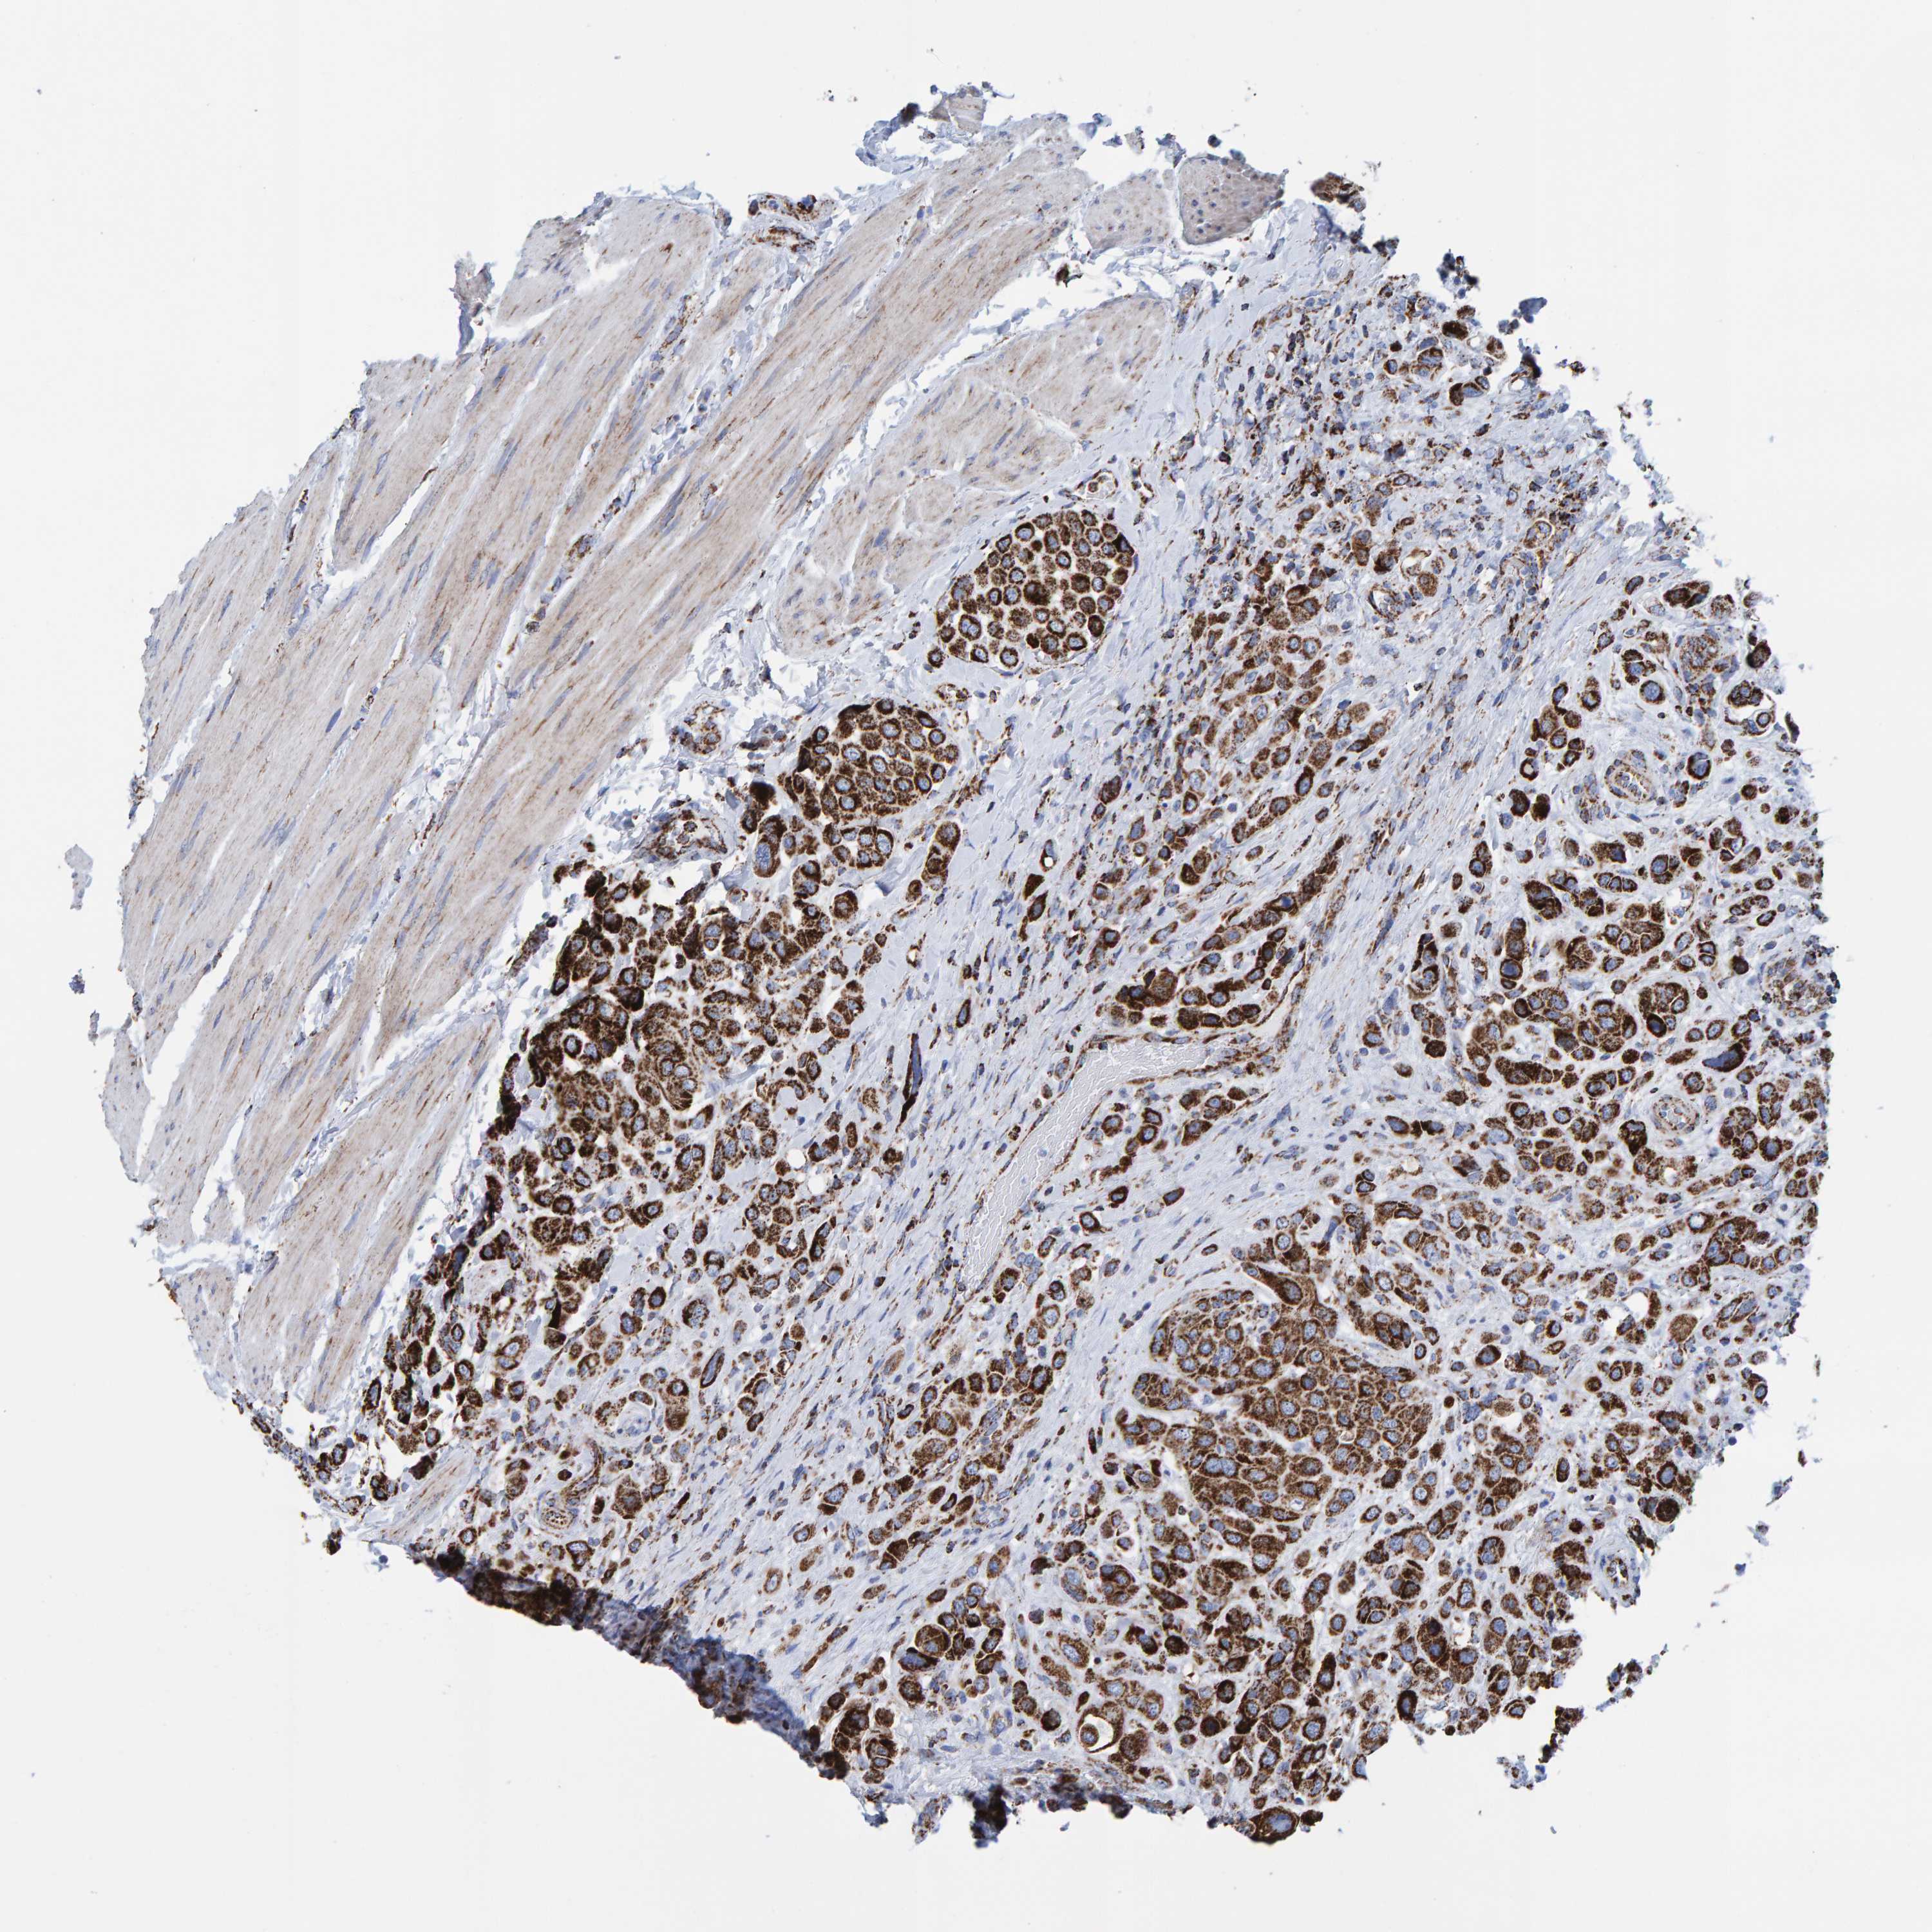

UROTHELIAL CANCER - Protein expressioni

A mouse-over function shows sample information and annotation data. Click on an image to view it in a full screen mode. Samples can be filtered based on level of antibody staining by selecting one or several of the following categories: high, medium, low and not detected. The assay and annotation is described here.

Note that samples used for immunohistochemistry by the Human Protein Atlas do not correspond to samples in the TCGA dataset.

Antibody stainingi

Antibody staining in the annotated cell types in the current human tissue is reported as not detected, low, medium, or high, based on conventional immunohistochemistry profiling in selected tissues. This score is based on the combination of the staining intensity and fraction of stained cells.

Each image is clickable and will lead to virtual microscopy that enables deeper exploration of all samples and also displays staining intensity scores, fraction scores and subcellular localization as well as patient and tissue information for each sample.

Antibody HPA022853

Antibody HPA023043

Antibody HPA023048

Staining

High

Medium

Low

Not detected

Intensity

Strong

Moderate

Weak

Negative

Quantity

>75%

75%-25%

<25%

None

Location

Nuclear

Cytoplasmic/membranous

Cytoplasmic/membranous,nuclear

Urothelial carcinoma, Low grade

Urothelial carcinoma, High grade